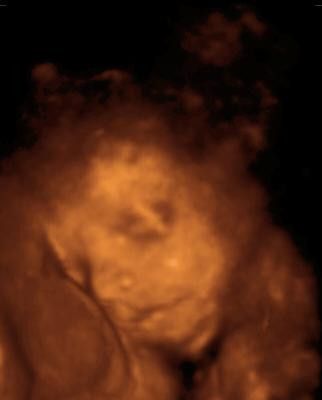

Tinchen´s Krümelchen 13. +1 (14. SSW)

13.10.2010

Krümel ist jetzt 8,7 cm groß. Das Herz hat ganz fleißig geschlagen. Und eine gratis Turnstunde gab es auch noch zu sehen.